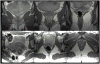

Methods: Magnetic resonance images of 15 healthy younger (aged 21-25 years) and 12 healthy older nulliparous women (aged >63 years) were selected to avoid the confounding effect of childbirth. Models were created from tracing outlines of the levator ani muscle in the coronal plane, and obturator internus in the axial plane using 3D Slicer v. 3.4. Muscle volumes were calculated using Slicer, while CSA was measured using Imageware™ at nine locations. The hypotheses were tested using repeated measures analysis of variance with P < 0.05 being considered significant.

Results: The effect of age did not reach statistical significance for the decrease in levator ani muscle maximum CSA or the decrease in volume (4.3%, P = 0.62 and 10.9%, 0.12, respectively). However, age did significantly adversely decrease obturator internus muscle maximum CSA and volume (24.5% and 28.2%, P < 0.001, respectively). Significant local age-related changes were observed dorsally in both muscles.